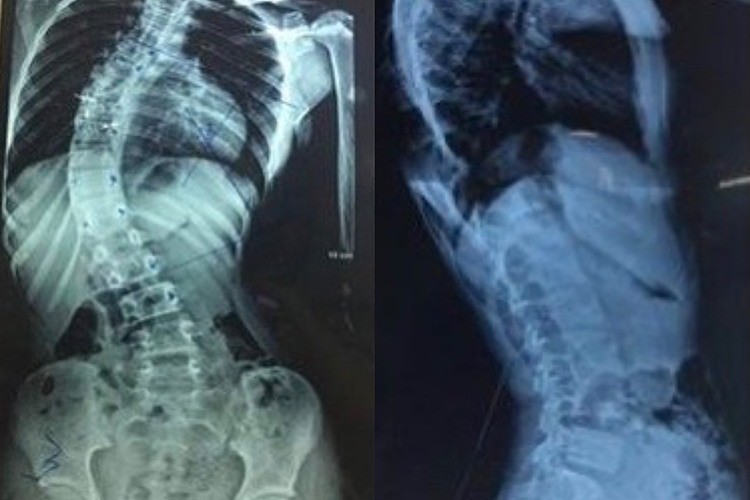

Nắn thẳng cột sống cong hơn 45 độ của bé gái

Trước đó, em không hề bị chấn thương hay té ngã gì. Các bác sĩ Khoa Ngoại Thần kinh, Bệnh viện Đa khoa Phú Thọ, ngày 11/8 cho biết các yếu tố làm cong vẹo cột sống ở độ tuổi này có thể do tư thế ngồi...